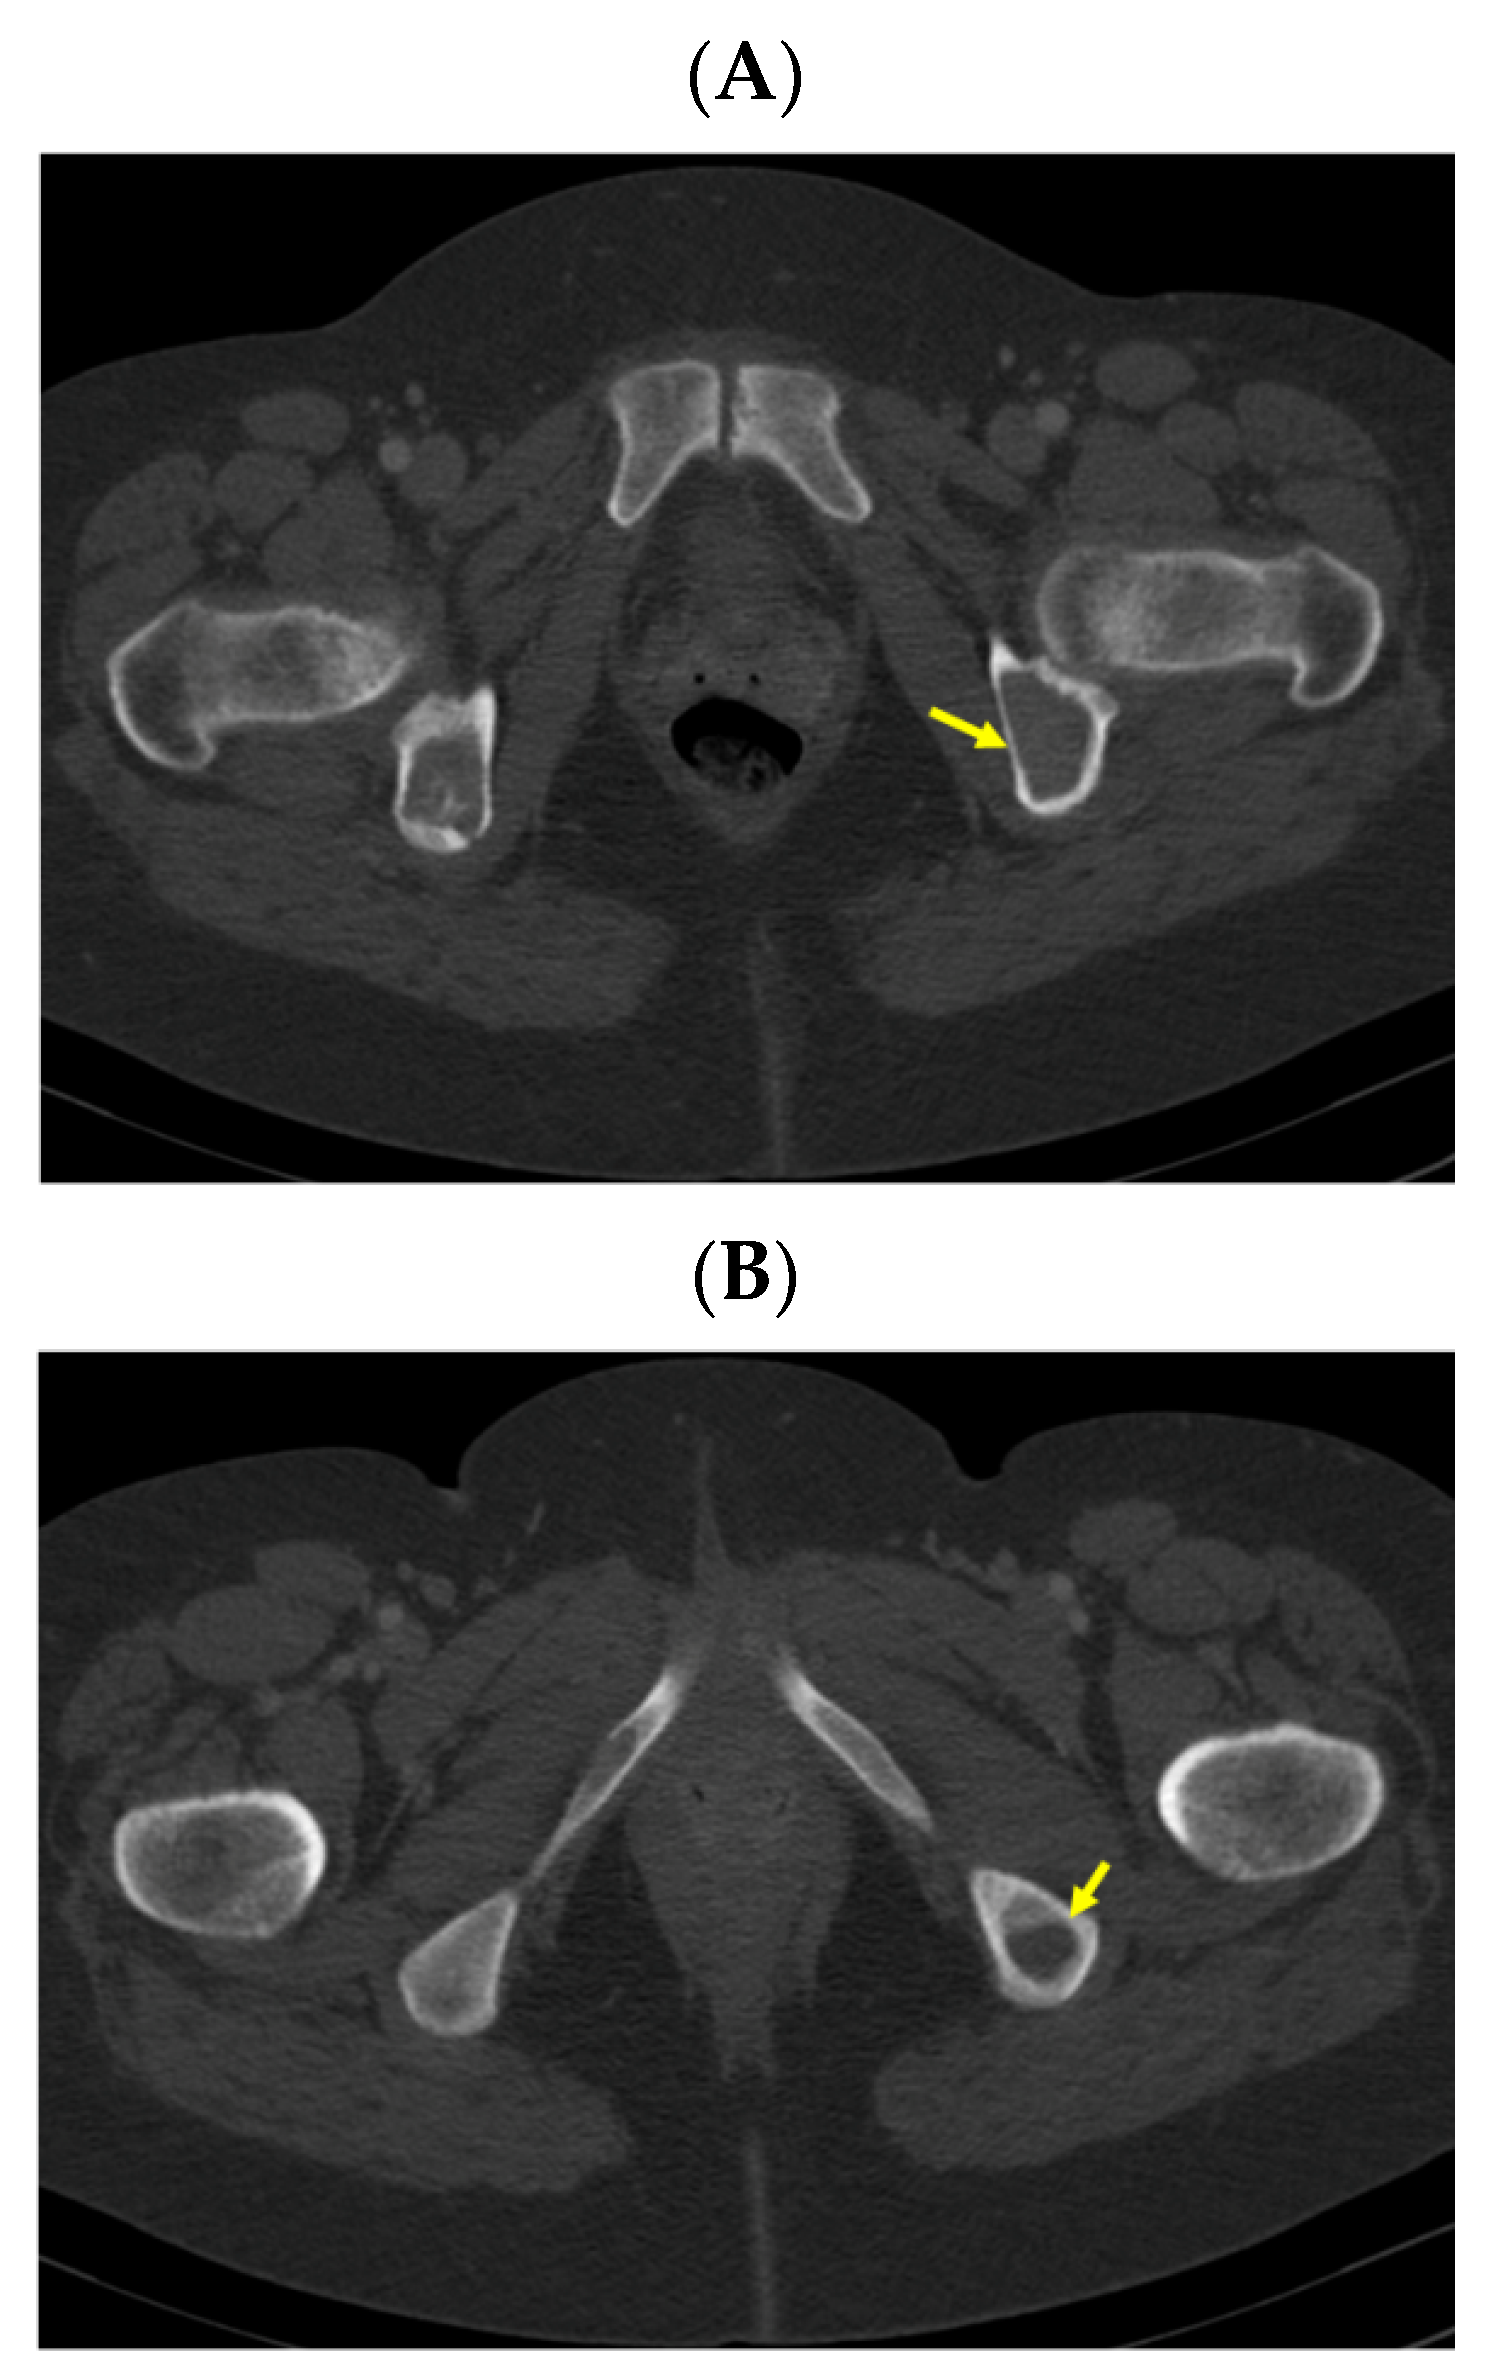

A pelvis CT scan confirmed the osteolytic lesions of the ischium and of the left coxal bone adjacent to the acetabular fossa, measuring 1.97 by 3.29 cm and 1.14 by 1.71 cm, respectively (brown tumors) (Figure 6).

Figure 6.

Pelvis CT scans showing other brown tumors: (A) osteolytic lesion of the left coxal bone adjacent to the acetabular fossa of 1.14 by 1.71 cm (axial plane); (B) osteolytic lesion of the left ischium of 1.97 by 3.29 cm (axial plane).